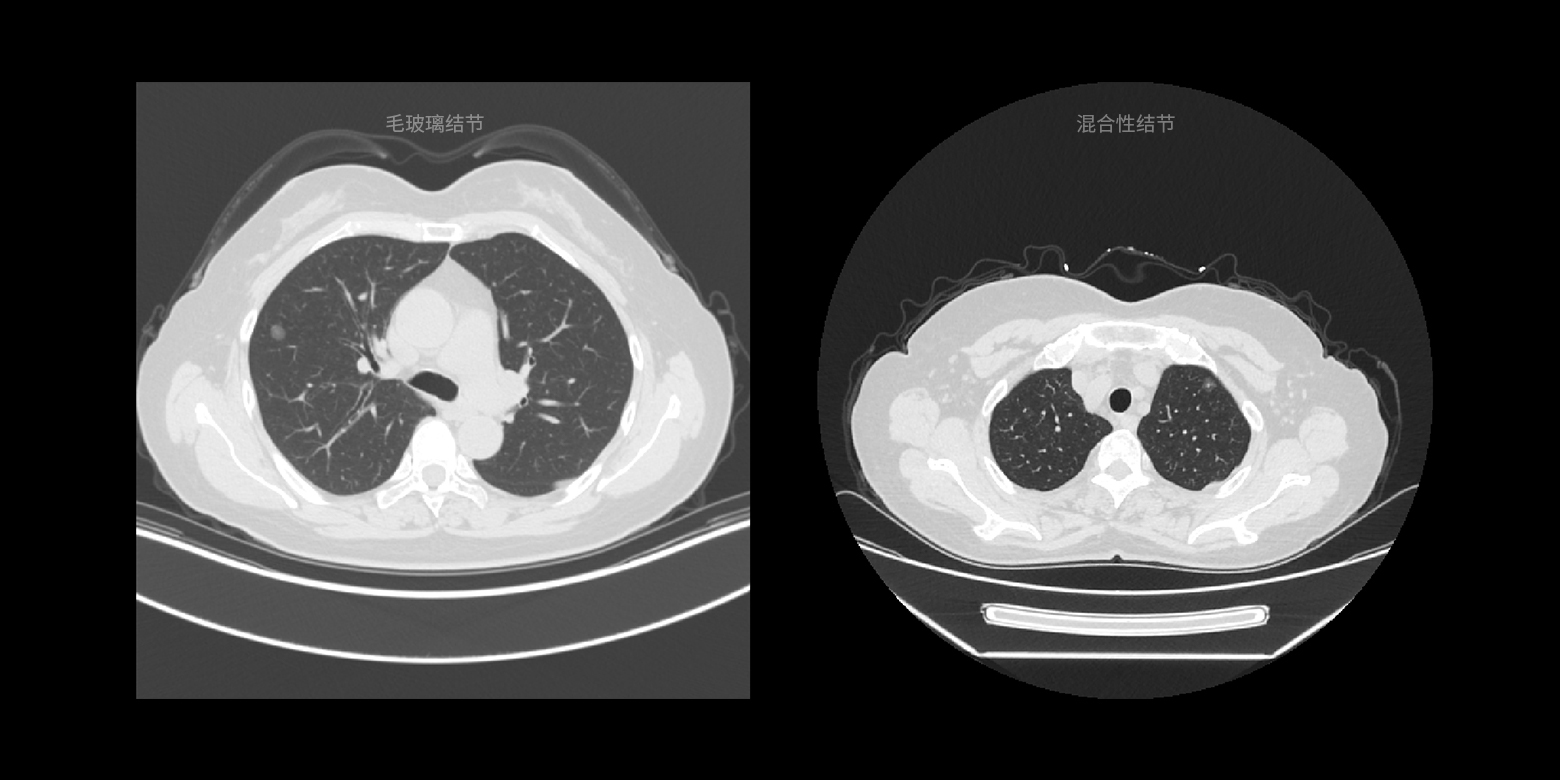

病灶类型鉴别

结合国际通用的诊断指南以及顶级医生的诊断经验,对临床诊断起到关键作用的病灶类型进行快速鉴别,降低相似病灶的误诊概率。

病灶类型鉴别

结合国际通用的诊断指南以及顶级医生的诊断经验,对临床诊断起到关键作用的病灶类型进行快速鉴别,降低相似病灶的误诊概率。